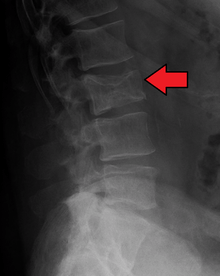

Bone pain affects almost 70% of patients and is the most common symptom.[11] Myeloma bone pain usually involves the spine and ribs, and worsens with activity. Persistent localized pain may indicate a pathological bone fracture. Involvement of the vertebrae may lead to spinal cord compression or kyphosis. Myeloma bone disease is due to the overexpression of receptor activator for nuclear factor κ B ligand (RANKL) by bone marrow stroma. RANKL activates osteoclasts, which resorb bone. The resultant bone lesions are lytic (cause breakdown) in nature and are best seen in plain radiographs, which may show "punched-out" resorptive lesions (including the "raindrop" appearance of the skull on radiography). The breakdown of bone also leads to release of calcium into the blood, leading to hypercalcemia and its associated symptoms.

The work-up of suspected multiple myeloma includes a skeletal survey. This is a series of X-rays of the skull, axial skeleton and proximal long bones. Myeloma activity sometimes appear as "lytic lesions" (with local disappearance of normal bone due to resorption), and on the skull X-ray as "punched-out lesions" (pepper pot skull). Magnetic resonance imaging (MRI) is more sensitive than simple X-ray in the detection of lytic lesions, and may supersede skeletal survey, especially when vertebral disease is suspected. Occasionally a CT scan is performed to measure the size of soft tissue plasmacytomas. Bone scans are typically not of any additional value in the workup of myeloma patients (no new bone formation; lytic lesions not well visualized on bone scan).

- Bone lesions (lytic lesions or osteoporosis with compression fractures)